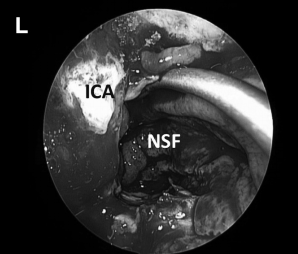

▼(K)使用TachoSil、纤维蛋白胶封闭颅腔

▼(L)使用鼻中隔瓣(NSF)完成封闭。CC,囊包膜;PFD,后颅窝硬脑膜;S,蝶鞍;T,肿瘤。

神经内镜手术“动态控制”的重要关键优势是,它允许外科医生逐步靠近目标并放大术野,同时减少鼻腔内手术器械操作之间的冲突。这在某些情况下如重要神经组织的解剖分离、肿瘤暴露中至关重要的,例如在颈内动脉附近钻孔、暴露视神经顶部或在硬膜内分离解剖过程中。此过程类似于在执行更细致的操作时使用显微镜进行放大。例如,在手术操作系列图中,我们可以了解当从骨质解剖分离颈内动脉ICA(A)、从硬脑膜上解剖病变包膜(D)或耳蜗下的骨质时,神经内镜与磨钻头的距离有多近(I)。该技术结合了耳鼻喉科和神经外科手势的优点。